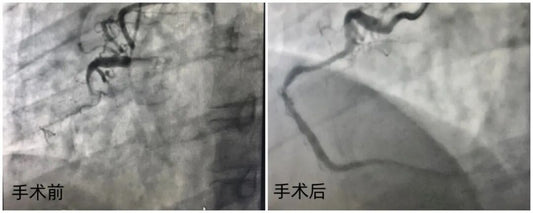

Technical Standards: Clinical Decision Pathways for "Intervention Without Implantation" in Complex Angulated CTOs

Fuwai Hospital demonstrates technical excellence in treating a 43-year-old patient’s complex CTO via a scaffold-free strategy. This case highlights the role of rigorous lesion preparation in achieving revascularization under complex...